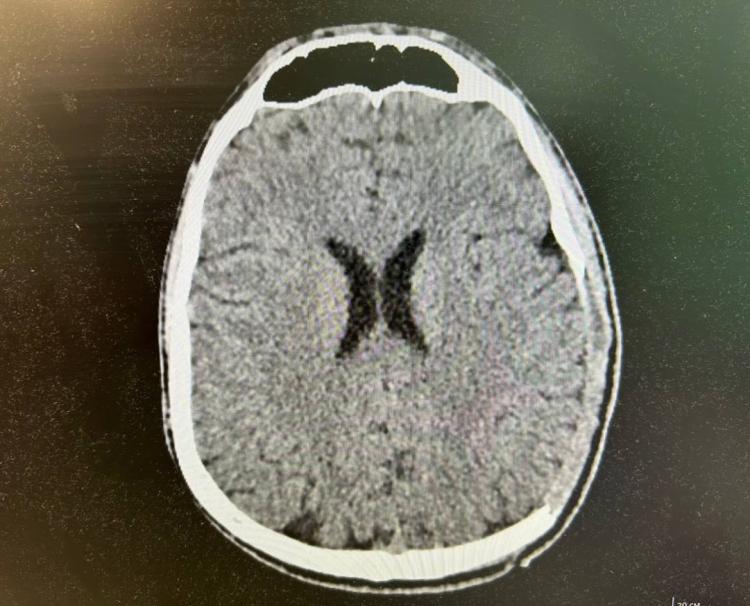

18-летний Артем, управлявший электросамокатом, столкнулся с автомобилем. Парня привезли в Тысячекоечную больницу в критическом состоянии, сообщает РИА VladNews со ссылкой на пресс-службу медучреждения.

Множественные травмы – тяжелый ушиб головного мозга, переломы костей черепа, открытый перелом голени и кисти – требовали немедленного вмешательства. Каждая секунда была на вес золота.

Команда реаниматологов, нейрохирургов и травматологов действовала слаженно, борясь за жизнь Артема. Экстренная обработка ран, остановка кровотечения, противошоковая терапия, сложнейшая нейрохирургическая операция по устранению последствий ЧМТ и остеосинтез для фиксации перелома голени – все это было проведено в условиях максимальной спешки.

«Любое промедление могло обернуться необратимыми последствиями, вплоть до летального исхода от кровоизлияния в мозг», – пояснил заведующий нейрохирургическим отделением Сергей Моисеенко.

После двух недель в реанимации, Артем начал долгий путь к выздоровлению, переходя из одного отделения в другое. Месяц интенсивного лечения дал свои плоды: молодой человек был выписан с обнадеживающей положительной динамикой. Впереди его ждет реабилитация и плановая операция по установке титановой пластины для восстановления целостности черепа.